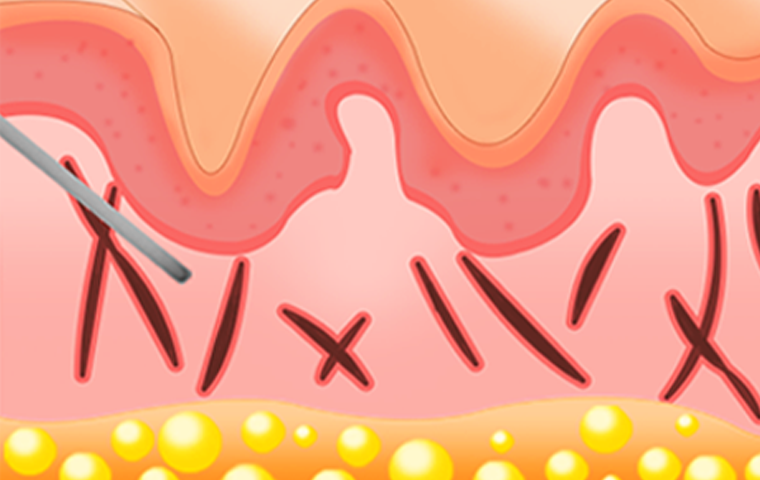

볼륨이 꺼진부위 & 여드름 흉터 & 주름이 있는

부위의 진피와 지방조직 사이에 주입합니다.